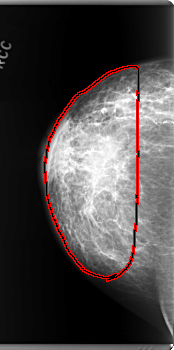

C_0159_1.RIGHT_CC

FILE: C_0159_1.RIGHT_CC.OVERLAY

TOTAL_ABNORMALITIES 1

ABNORMALITY 1

LESION_TYPE MASS SHAPE IRREGULAR MARGINS ILL_DEFINED

ASSESSMENT 5

SUBTLETY 5

PATHOLOGY MALIGNANT

TOTAL_OUTLINES 1

BOUNDARY